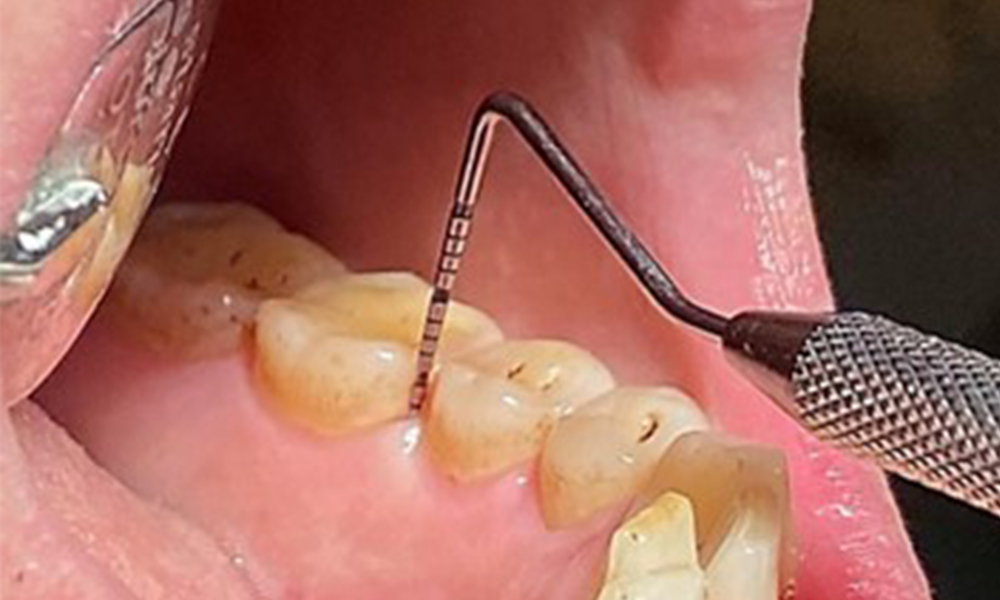

At 1 to 3 mm, the clinical probing depths were within the physiological range. Maxillary recessions of up to 1 mm were observed from 13 to 16 and 23 to 27. The BOP was 15%.

Pocket probing (BOP) with depiction of tooth 36 lingual

Fig. 7 Pocket probing (BOP) with depiction of tooth 36 lingual, © Dr R. Krapf